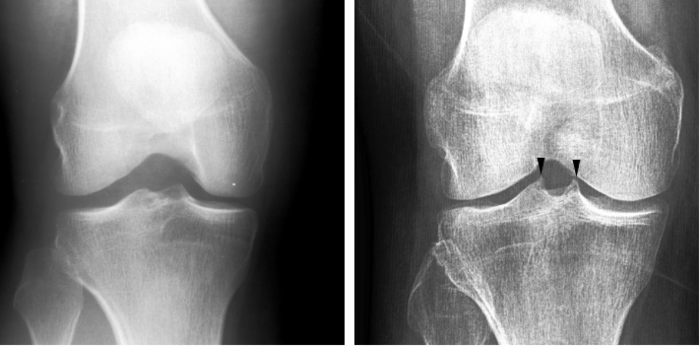

Researchers focused on patients with mild-to-moderate osteoarthritis in the medial compartment of the knee, the inner side of the joint, which typically bears more weight than the outer, lateral compartment.

One year later, participants reported on their knee pain and underwent a second MRI to quantitatively assess cartilage damage. Those in the intervention group experienced reduced pain and showed less cartilage degradation compared with the control group.